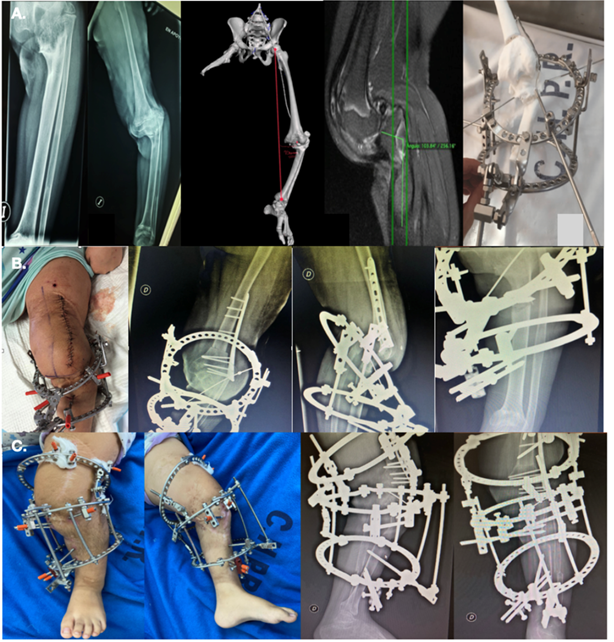

Periodo 2013-2018: La paciente presento una buena evolución de las partes blandas con epitelizacion de las lesiones, pero sufrió graves retracciones cicatriciales. A nivel osteoarticular, el muñón del MID evoluciono adecuadamente, pero con tendencia a la flexión, en MII presentaba deformaciones angulares severas debido a la formación de puentes fisarios consecuencia de la CID. En la radiografía se evidencia una deformidad multiapical de la tibia dado por un varo severo (50°), recurvatum (60°), acortamiento de tibia, y un varo del tobillo. Se observan puentes fisarios central y periférico (medial) destacamos el signo de “ball and socket” 8) característico de este tipo de lesiones

Periodo 2020 - 2022. La paciente pierde la capacidad de marcha debido a la progresiva flexión de rodilla. La progresión del arresto fisario anterior generó una deformidad severa en la tibia proximal simulando una perdida de congruencia articular. Se solicitaron tomografía con reconstrucción 3D, resonancia magnética, goniometría en la revaloración imagenológica completa.

Hallazgos Imagenologicos: Eje mecánico del miembro (MAD): 30 mm.

Eje mecánico y anatómico de femur: mLPFA 70°.aMPFA 73°. mLDFA 98°. aLDFA 91°. Valgo fémur proximal, varo fémur distal, deformidad monoapical de femur 23° antecurvatum. Eje mecánico y anatómico de tibia: mMPTA: 46°. aMPTA 43°. mLDTA 66°. aLDTA 112°. Deformidad biapical tibia proximal 50°. Tibia distal varo 32°. Deformidad monoapical tibia proximal recurvatum 60°.

Fig 1: A. Necrosis inicial de MMII. B. Secuelas Osteoarticulares SM/CID. C. Radiografías evidenciando deformaciones angulares severas. * signo “ball and socket”

Se propuso realizar osteotomía a nivel del centro de rotación y angulación de la deformidad (CORA) y corrección en agudo de fémur distal utilizando fijación interna con placa bloqueada. Se planifico osteotomía por fuera del CORA y corrección progresiva con método de Ilizarov9 en tibia proximal. Para la adecuada planificación preoperatoria se confecciono un biomodelo 3D a medida replicando la deformidad ósea.

Primera intervención quirúrgica se realizó liberación del nervio ciático poplíteo externo (CPE) y fasciotomia profiláctica del compartimento anteroexterno. Osteotomía de peroné proximal protegiendo el trayecto del nervio CPE y posteriormente la osteotomía femoral en él CORA con corrección en agudo del antecurvatum, varo y rotación interna, la fijación se realizo con placa bloqueada.

Colocación del montaje Ilizarov prearmado con 2 aros en tibia y osteotomía percutánea distal al CORA.

En el postoperatorio se presentó como dificultad el inicio en la apertura de la osteotomía en tibia. Se aumentó el ritmo de corrección logrando así la distracción. No fueron necesarias nuevas cirugías. Se ajustó el montaje con un ritmo de distracción a razón 1 mm por día. A pesar de la mejoría de la deformación angular la paciente mantiene una contractura fija en flexión de rodilla de 18°.

En la segunda intervención quirúrgica se coloco un aro de 160 de Ilizarov en fémur para corrección progresiva del flexo, y se realiza desrrotación de tibia junto con la osteotomía del peroné distal, realizando rotación interna de 10° (Fig. 2).

Fig 2: A. Planificación preoperatoria. B. Primer cirugía. C. Segunda cirugía con agregado de anillo de Ilizarov